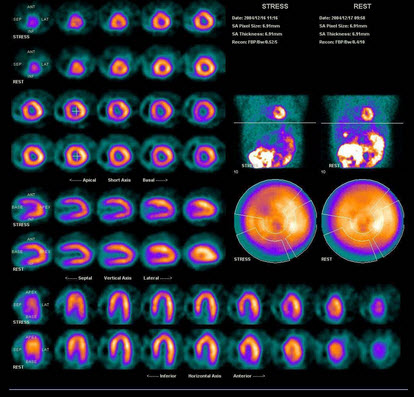

37、多项选择题

男性,41岁,劳力性心绞痛,有高血压、高血糖、高血脂,行99Tcm-MIBI心肌运动、静息显像如图,最可能的诊断是()

A.左心室前壁、下壁心肌缺血

B.冠心病

C.扩张型心肌病

D.代谢综合征

E.高血压心脏病